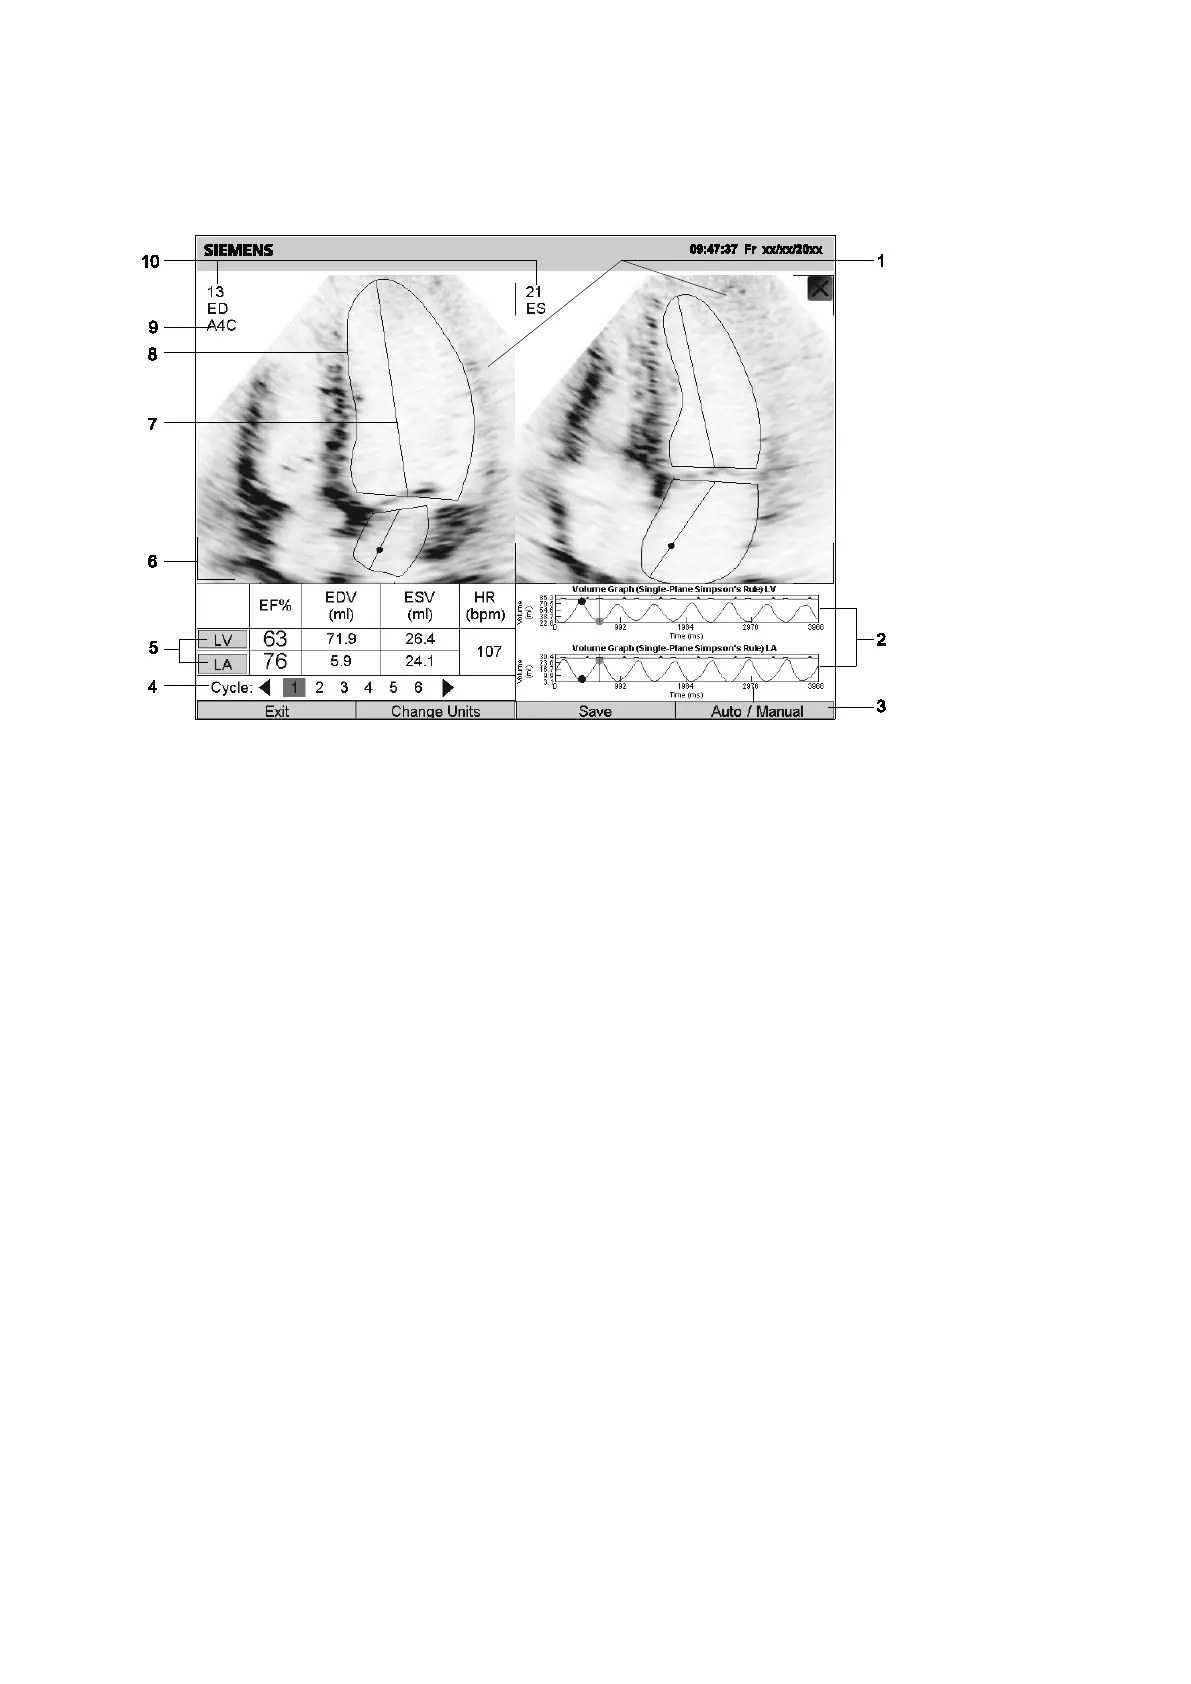

Example of syngo Auto Left Heart Screen

The program displays the syngo Auto Left Heart screen when you select the image view.

1 Image display area

2 Volume graphs

3 Location of buttons

4 Heart Cycle indicator

5 Calculation data

6 Frame corner indicating the active image

7 Long axis

8 Outline of the structure

9 Current view and image orientation

10 Frame number